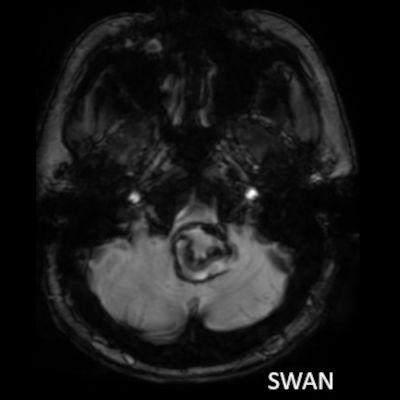

- A. Posterior fossada, T2A, T1A görüntü ve SWAN sekanslarda, 3.5 cm boyutta, düzgün sınırlı, T1A hiperintens, T2A hipointens heterojen iç yapıda kitlesel lezyon izleniyor (çember). Lezyonun serebellum ve kraniyoservikal bileşkeye bası etkisi mevcuttur (ok). Lezyon periferinde T1A, T2A ve SWAN görüntülerde hiperintens tubuler yapı bulunmaktadır (ok). Bu yapı intralezyonel “yılanvari eksantrik vasküler’’ yapıdır.

- T2 ve SWAN genellikle santral-çevresel duyarlılık artefaktları görülür.